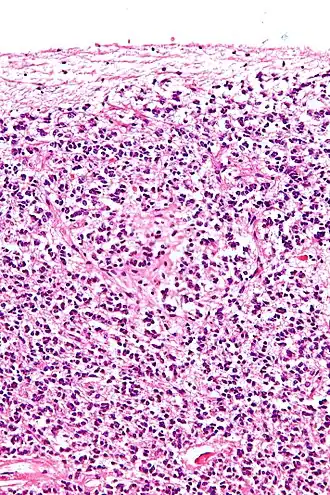

Cross-section of pineal gland displaying pinealocytes and other cells